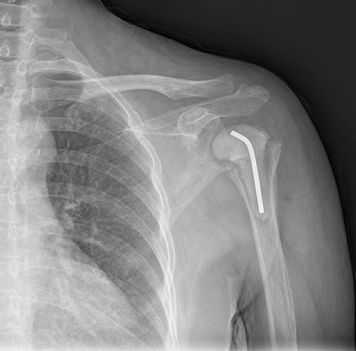

骨一科主任姜文学带领团队为康女士做了左肩关节清理术,清除了康女士左侧肱骨头被结核菌破坏的病损组织。

姜文学介绍,骨结核虽然不具有传染性,但复发后会造成进一步的骨破坏,因此需要先控制好结核才能进行关节置换。因此,在清除了病损组织后,姜文学又放置了骨水泥在康女士的关节位置。

“这台手术过后3个月我们才给患者做肩关节置换术,主要是为了控制患者的结核?!苯难Ы樯?,骨结核虽然不具有传染性,但复发后会造成进一步的骨破坏,因此需要先控制好结核才能进行手术。